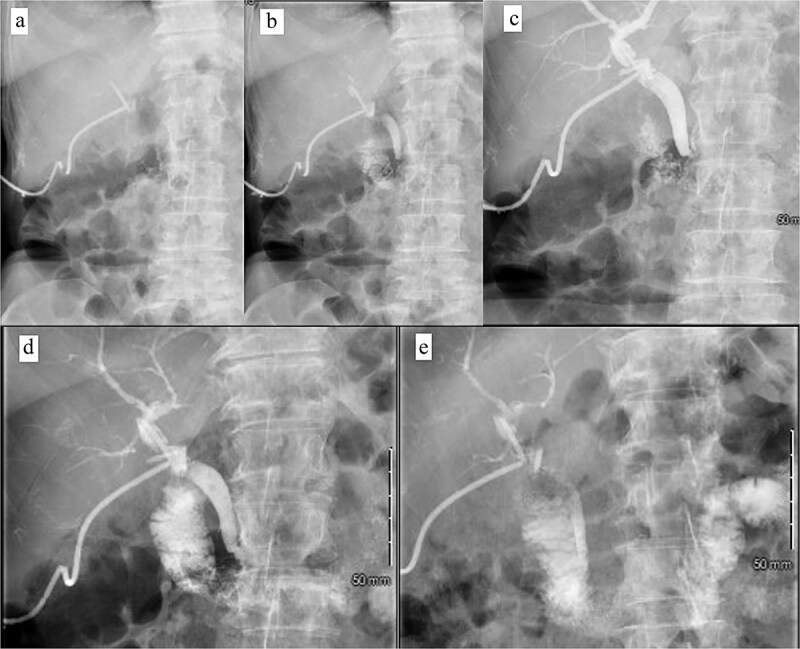

Patient was brought to the OR, induced, and the peritoneum was accessed via optical view trocar. After the critical view of safety was obtained, the cystic duct was partially transected and a 6-French ureteral catheter was threaded through the duct and into the CBD. Initial cholangiogram showed complete obstruction of the distal CBD. A 0.035 guidewire was advanced through the ureteral catheter. The ureteral catheter was then exchanged for a 9 × 40 mm long vascular balloon catheter. The balloon was then centered at the ampulla of vater and inflated to its nominal pressure for 5 min. A small indentation was noticed at the level of the ampulla once the balloon was fully insufflated, as expected. The completion cholangiogram showed prompt evacuation of contrast into the duodenum. However, numerous “floating” filling defects continued to be present (Fig. 4). The decision was thus made to leave a T-tube in place via a 1-cm longitudinal choledochotomy. The incision was reapproximated around the t-tube with interrupted 4–0 PDS. The vascular balloon catheter was removed, the cystic duct was completely transected, and the gallbladder was dissected off the liver bed.

Patient was discharged home on POD 7 following IV antibiotic completion (Fig. 5). Patient was seen in the ER 1 week later for drainage around the T-tube. Tube study confirmed resolution of CBD obstruction and the patient was discharged from the ER (Fig. 6).